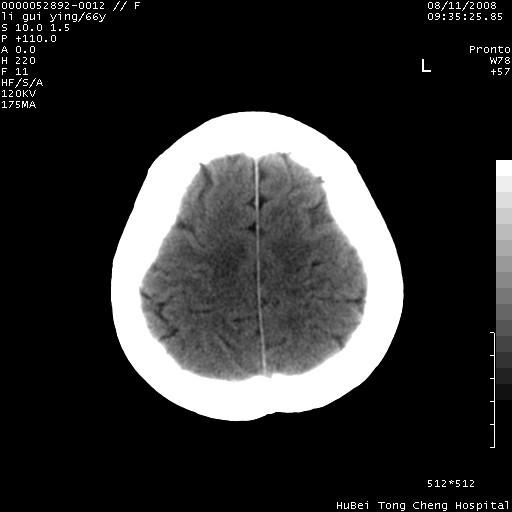

以下是引用yangyudong333在2008-8-12 12:22:00的发言:[br]1.病灶呈圆形[br]2.周围无水肿带[br]3.密度不均匀,内有点状钙化[br]4.无占位效应[br] 考虑良性占位性病变,血管瘤可能性大